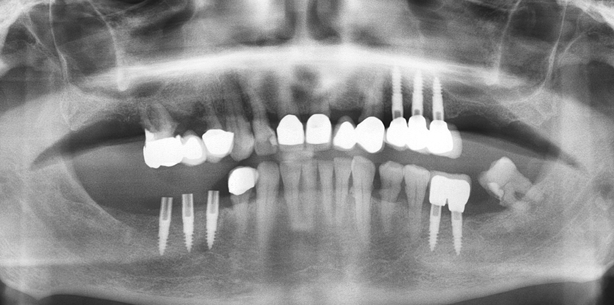

Einem 77-jährigen Patienten (Nicht-raucher, Blutdruck eingestellt) wurden zwölf Wochen nach Extraktion des Zahnes 45 alio logo drei einteilige Implantate (nature Implants) flapless primärstabil inseriert. Nach der achtwöchigen Einheilphase wurde der Zirkonkronenblock 45 und 46 zementiert. Einer erneuten Bisskontrolle folgend, konnte nach weiteren vier Wochen Soft-Loading die Behandlung abgeschlossen werden.

Die anschließende Röntgenkontrolle erfolgte mittels OPG (Abb. 6). Hierbei wurde die Lage der Implantate zum Nervus mandibularis sowie zum Foramen mentalis und die Implantattiefe im Knochen kontrolliert und dokumentiert. Eventuelle Korrekturen, die nach der Röntgenkontrolle durchgeführt wurden, wie eine tiefere Insertion der Implantate, werden im OP-Protokoll schriftlich fixiert. Nach dem Aufbringen der PEEK-Abformkappen erfolgte die geschlossene Abformung mit Impregum (Abb. 7). Als Provisorium diente eine flache Schienung der Implantate mit Tetric Flow.